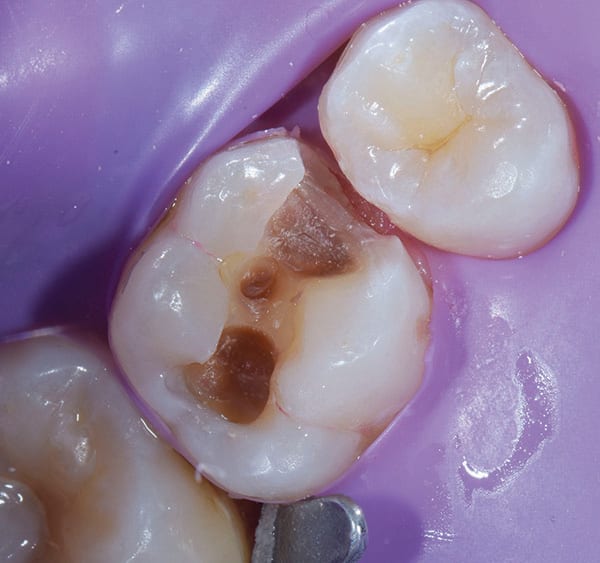

A 22-year-old patient presented for a re-care examination during which a preexisting occlusal composite restoration on tooth No. 14 was found to be undermined and fractured. It was not clear how long ago the composite had been placed. Although caries was clinically evident marginally and on the mesial aspect of the tooth (Figure 1), the patient did not report experiencing any sensitivity associated with the tooth or that area of the dentition. The patient was advised of the issue, shown the area of decay, and agreed to re-treatment with a Class II composite restoration.

Once the operative field was isolated, a No. 557 carbide bur was used in a high-speed handpiece to efficiently remove the existing composite restoration and extend the preparation mesially. The Class II preparation was then refined using a fine diamond chamfer bur. Initial caries removal was performed using a round carbide bur in a slow-speed attachment (Figure 2). After initial caries removal, a caries indicating solution (Seek™ Caries Indicator, Ultradent) was used to stain any suspected remaining caries (Figure 3).4 Caries indicating solutions target demineralized dentin with a highly visible stain, providing an efficient and effective means of ensuring that only the infected dentin is subsequently removed, leaving the affected dentin behind (Figure 4).